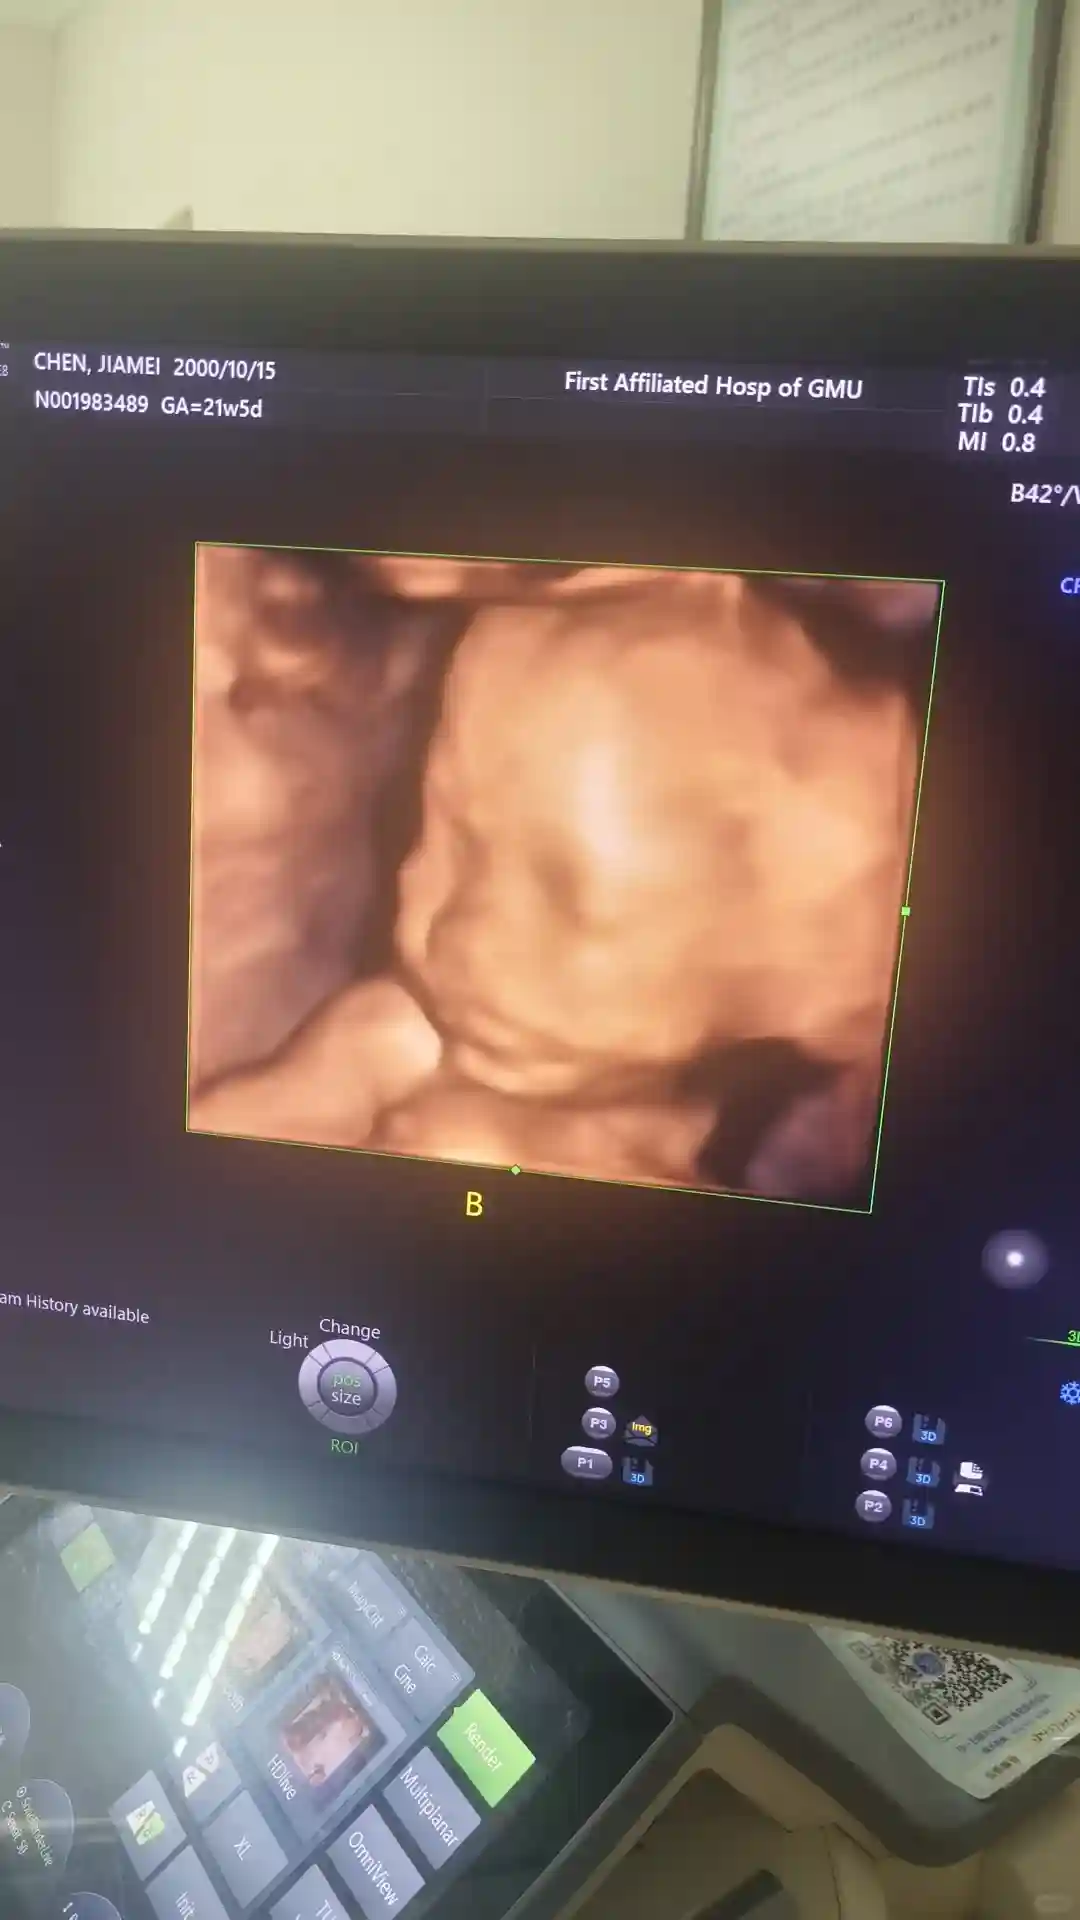

调整方案 第三次移植两枚胚胎 终于成功 前期血值翻倍不好很焦虑 都是胡主任的一句 没事有我在该用的药都用上了 接下来的就是要相信自己相信宝宝 因为离得离医院近 胡主任称得上是我的定海神针 经常有事没事跑去找主任聊聊天 天天问一大堆罗里吧嗦的问题 也从来不嫌烦 称得上是“老油条”了 正常情况一般12周左右就生殖科毕业 我一直都有各种各样不一样的问题硬生生的拖到16周才彻底毕业 回家之前主任也给我开好了各种防宫缩止血的药 所以有的时候想想能遇到一个有责任心的医生真的很幸运

接下来就希望我的宝宝能够健健康康出生 等他们满月之后带他们"回家"去看看